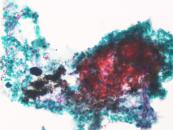

第35回日本臨床細胞学会九州連合会学会(宮崎)スライドカンファレンス症例3

種別:呼吸器

出題:福岡大学病院 病理部・病理診断科 濵﨑 慎 先生

| 年齢 | 80歳代 | 性別 | 男性 |

| 採取部位 | 左肺下葉 | 採取方法 | 腫瘍捺印細胞診 |

既 往 歴:労作性狭心症(バイパス術後)、高血圧症、高脂血症

生 活 歴:喫煙40本/日×49年

現 病 歴:労作性狭心症(バイパス術後)のフォロー中に貧血を指摘、精査中に左肺下葉に腫瘤を認め、確定診断目的で切除の方針となった。

| 正解 | 2.腺癌 |

| 1.扁平上皮癌 | 8件 | (8.2%) | |

| 2.腺癌 | 39件 | (40.2%) | |

| 3.大細胞神経内分泌癌 | 27件 | (27.8%) | |

| 4.悪性胸膜中皮腫 | 6件 | (6.2%) | |

| 5.悪性黒色腫 | 17件 | (17.5%) | |

| 投票総数 | 97件 | (100%) |